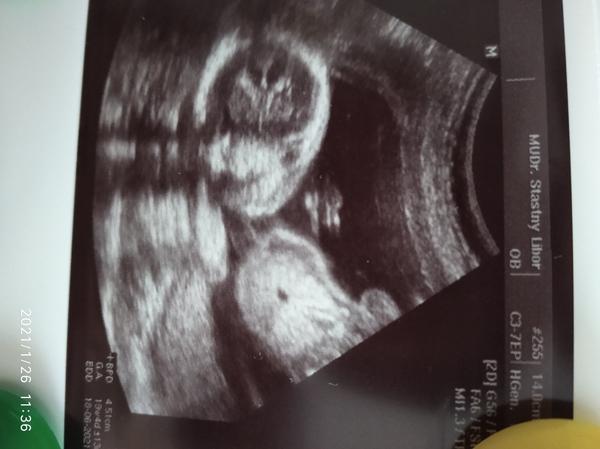

@lili1688 Pokud jste pozorovala utz, tak jste si jiste vsimla, ze se miminko ruzne hybe a doktor zameruje ruzne casti tela nebo je dokonce prosviti.

To, co mate zakrouzkovane muze byt cokoli co se vyskytuje okolo hrudniku nebo bricha. Miminko se zrovna hybalo a doktor udelal screen ve chvili, kdy se tam proste zobrazilo “tohle”.

Pohlavi to urcite neni a dal je asi jedno co to je, ne? 🤷🏼♀️